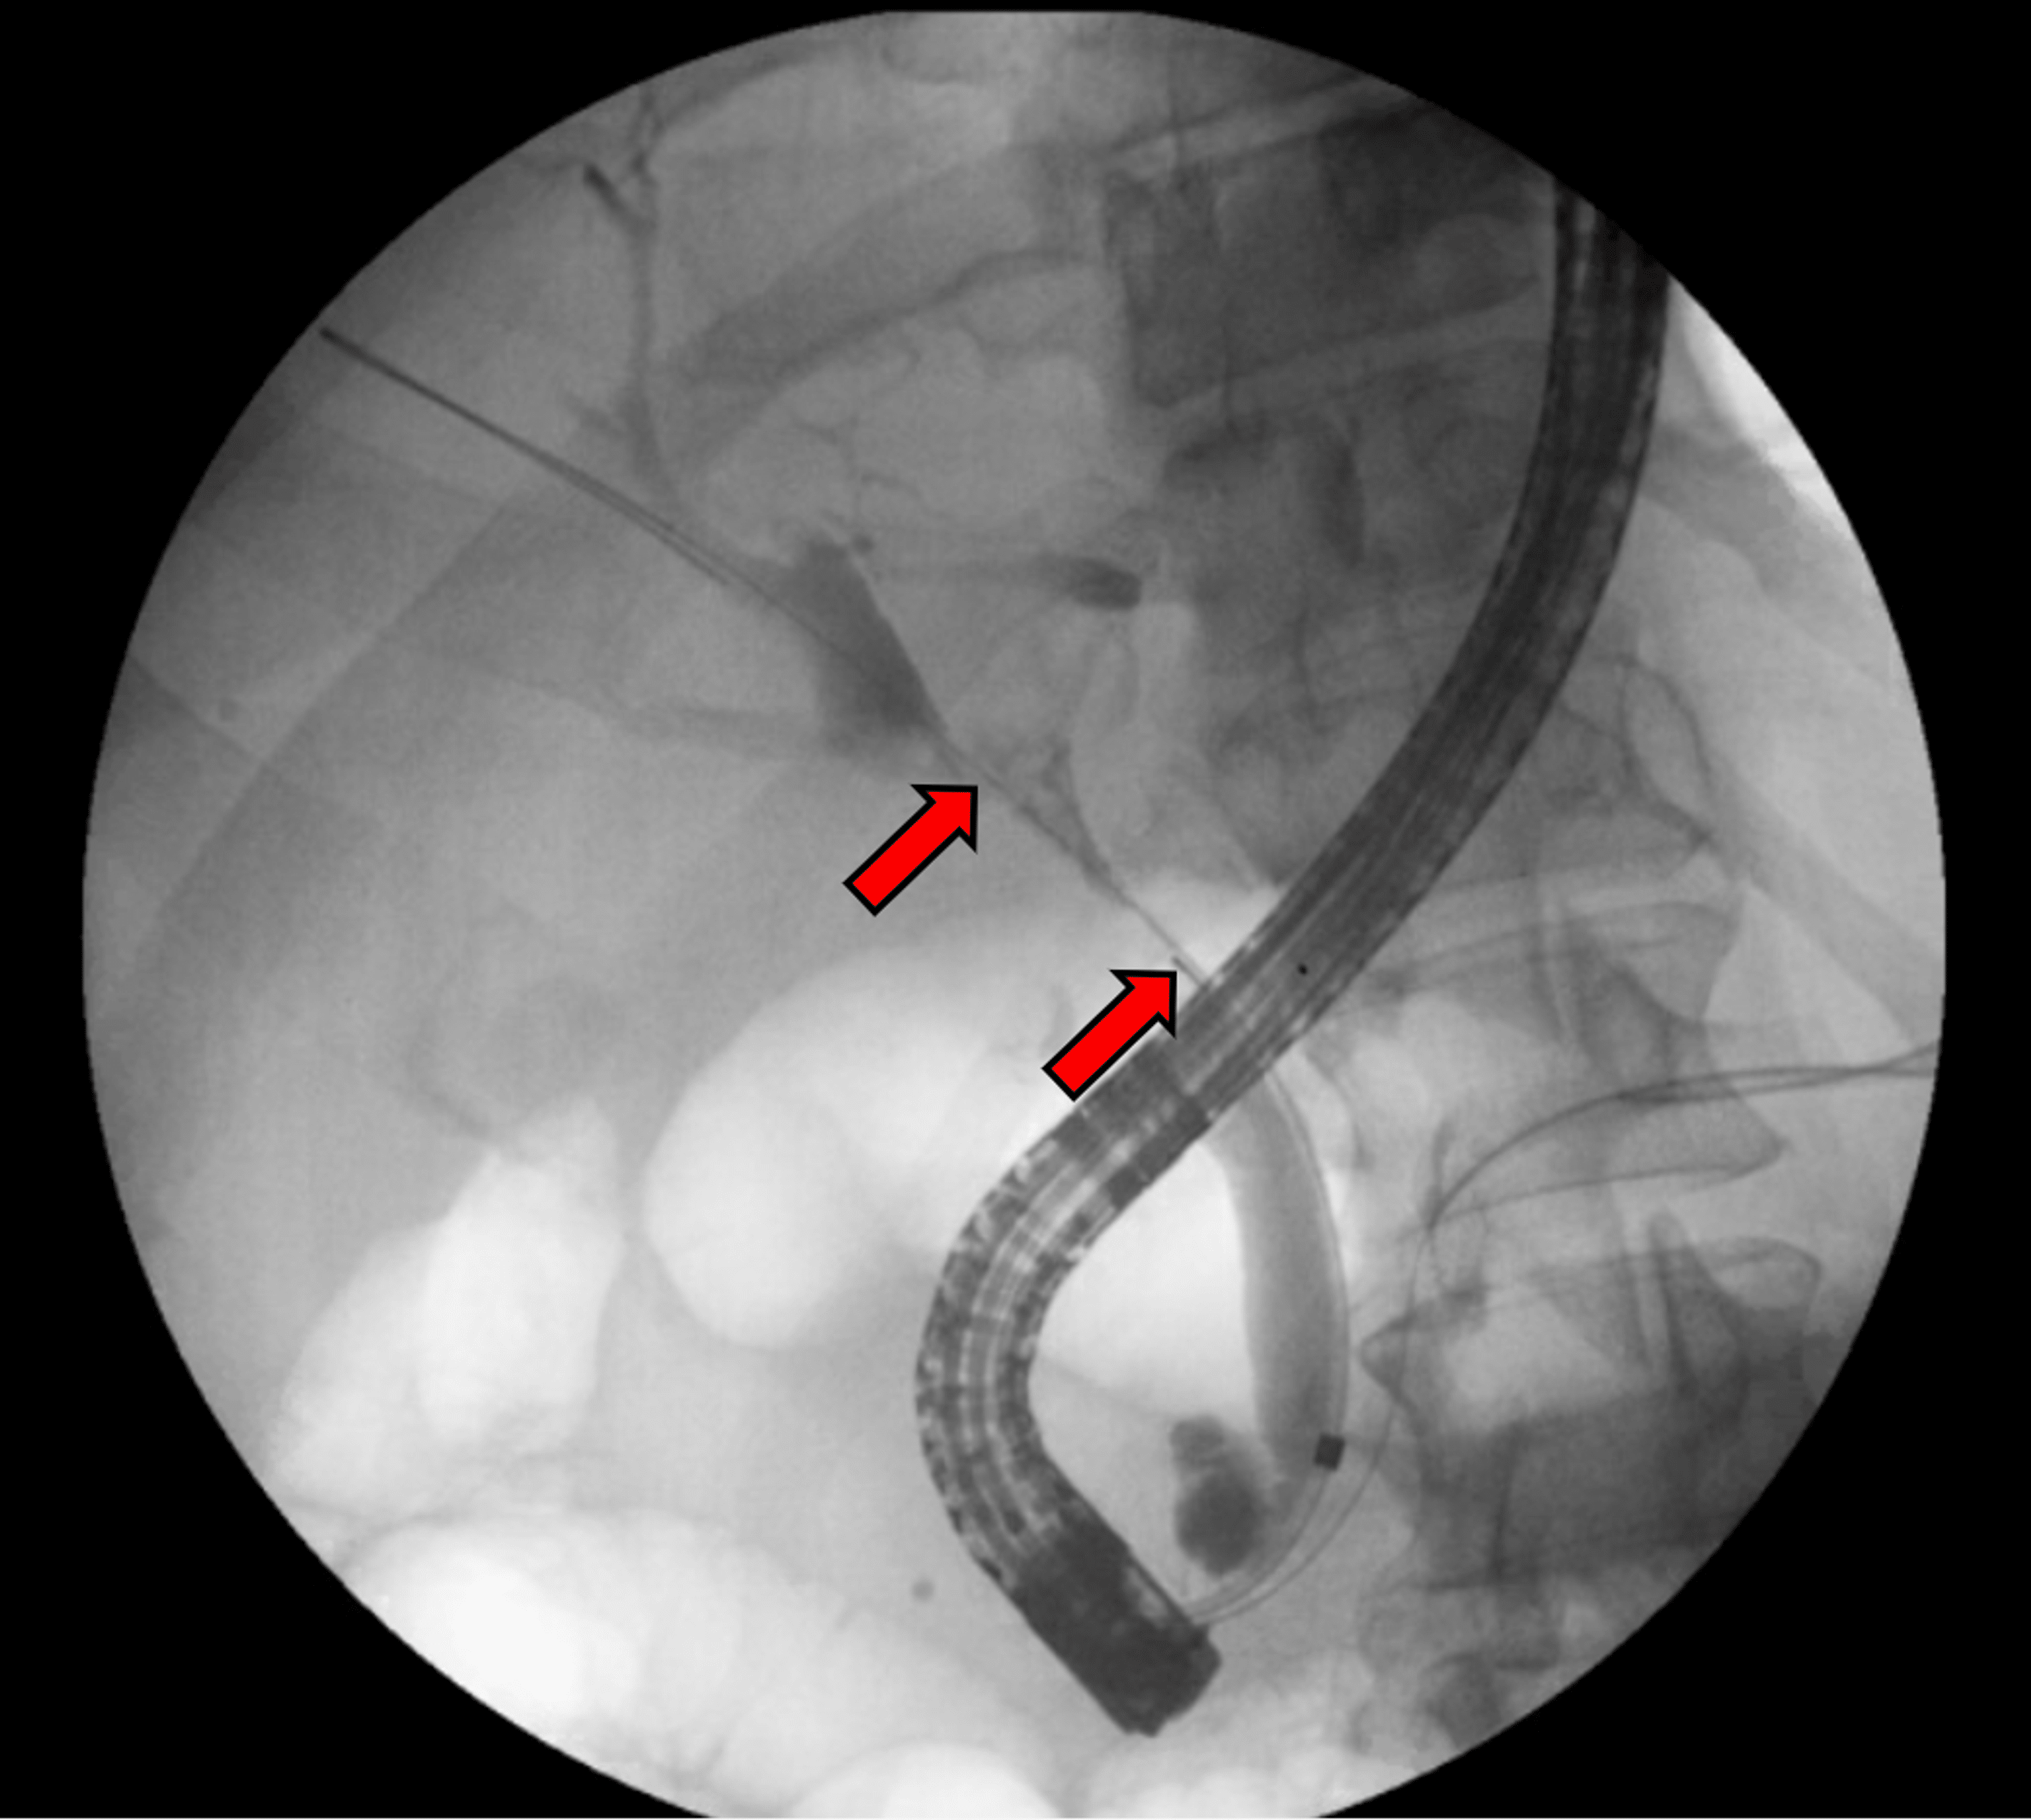

Optimizing Cholangiography When Performing Endoscopic Retrograde Endoscopic Retrograde Cholangiopancreatography Endoscopic retrograde cholangiopancreatography, or ercp, is a procedure to diagnose and treat problems in the liver, gallbladder, bile ducts, and pancreas. Learn why an ercp is done,. Endoscopic retrograde cholangiopancreatography (ercp) is an invasive procedure used for the diagnosis and treatment of obstruction in the biliary system. It is usually performed by a skilled gastroenterologist (specialist in digestive system disorders).. Endoscopic Retrograde Cholangiopancreatography.

From www.researchgate.net